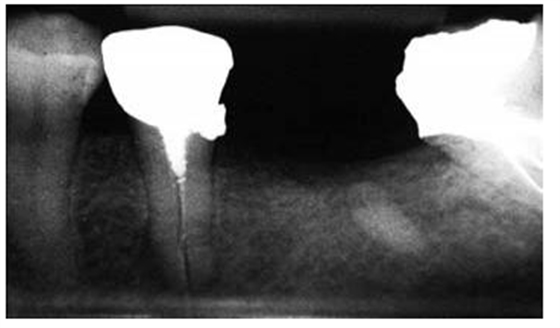

圖4:下頜第二前磨牙的根尖片,經(jīng)由螺紋樁進(jìn)行修復(fù),導(dǎo)致根折

5:下頜第二磨牙牙根穿孔的根尖片,樁道預(yù)備的器械未與根管壁相平行

研究結(jié)果表明牙根折斷是樁核修復(fù)失敗的第二個(gè)最為常見(jiàn)的原因。多個(gè)原因已經(jīng)被證實(shí)與牙根折斷潛在相關(guān),其中包括大直徑的樁修復(fù),短樁和帶螺紋的樁(圖 4)。臨床上推薦樁的直徑不能超過(guò)牙根直徑的1/3,并且樁直徑應(yīng)當(dāng)與牙根的平均尺寸成比例地相關(guān)。

對(duì)于牙體解剖、牙根結(jié)構(gòu)、形態(tài)及其變異的良好理解,同時(shí)使用恰當(dāng)?shù)念A(yù)備方向,能夠幫助牙醫(yī)在樁道預(yù)備過(guò)程中避免出現(xiàn)過(guò)多的切削牙體組織和牙根穿孔。預(yù)備樁道時(shí),器械的方向必須與根管的方向相平行(圖 5)。